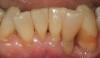

Пациентка 45 лет обратилась в клинику с целью санации полости рта. Наибольшую обеспокоенность у нее вызывали чувствительность зубов 4.5 и 4.7 к термическим раздражителям и неудовлетворенность эстетикой пломбировочного материала на зубе 4.7.

В зубе 4.5 необходимо было произвести лечение кариеса, а в зубе 4.7 – заменить пигментированный пломбировочный материал (рис. 1).